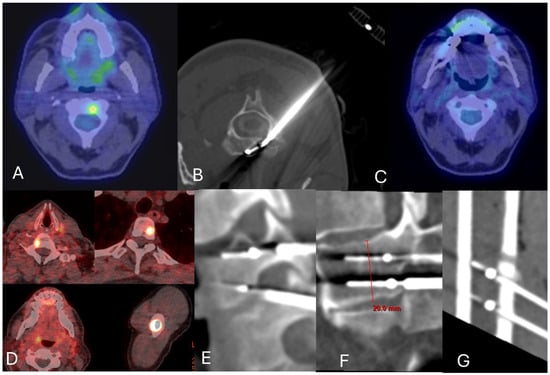

4. Radiofrequency Ablation (RFA) and Microwave Ablation (MWA)

4.1. RFA

- Tomasian, A.; Hillen, T.J.; Chang, R.O.; Jennings, J.W. Simultaneous Bipedicular Radiofrequency Ablation Combined with Vertebral Augmentation for Local Tumor Control of Spinal Metastases. Am. J. Neuroradiol. 2018, 39, 1768–1773. [Google Scholar] [CrossRef] [PubMed]